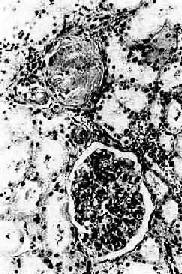

图8-12 高血压病之肾

肾小球入球小动脉管壁玻璃样变性,肾小球纤维化,玻璃样变 ×180